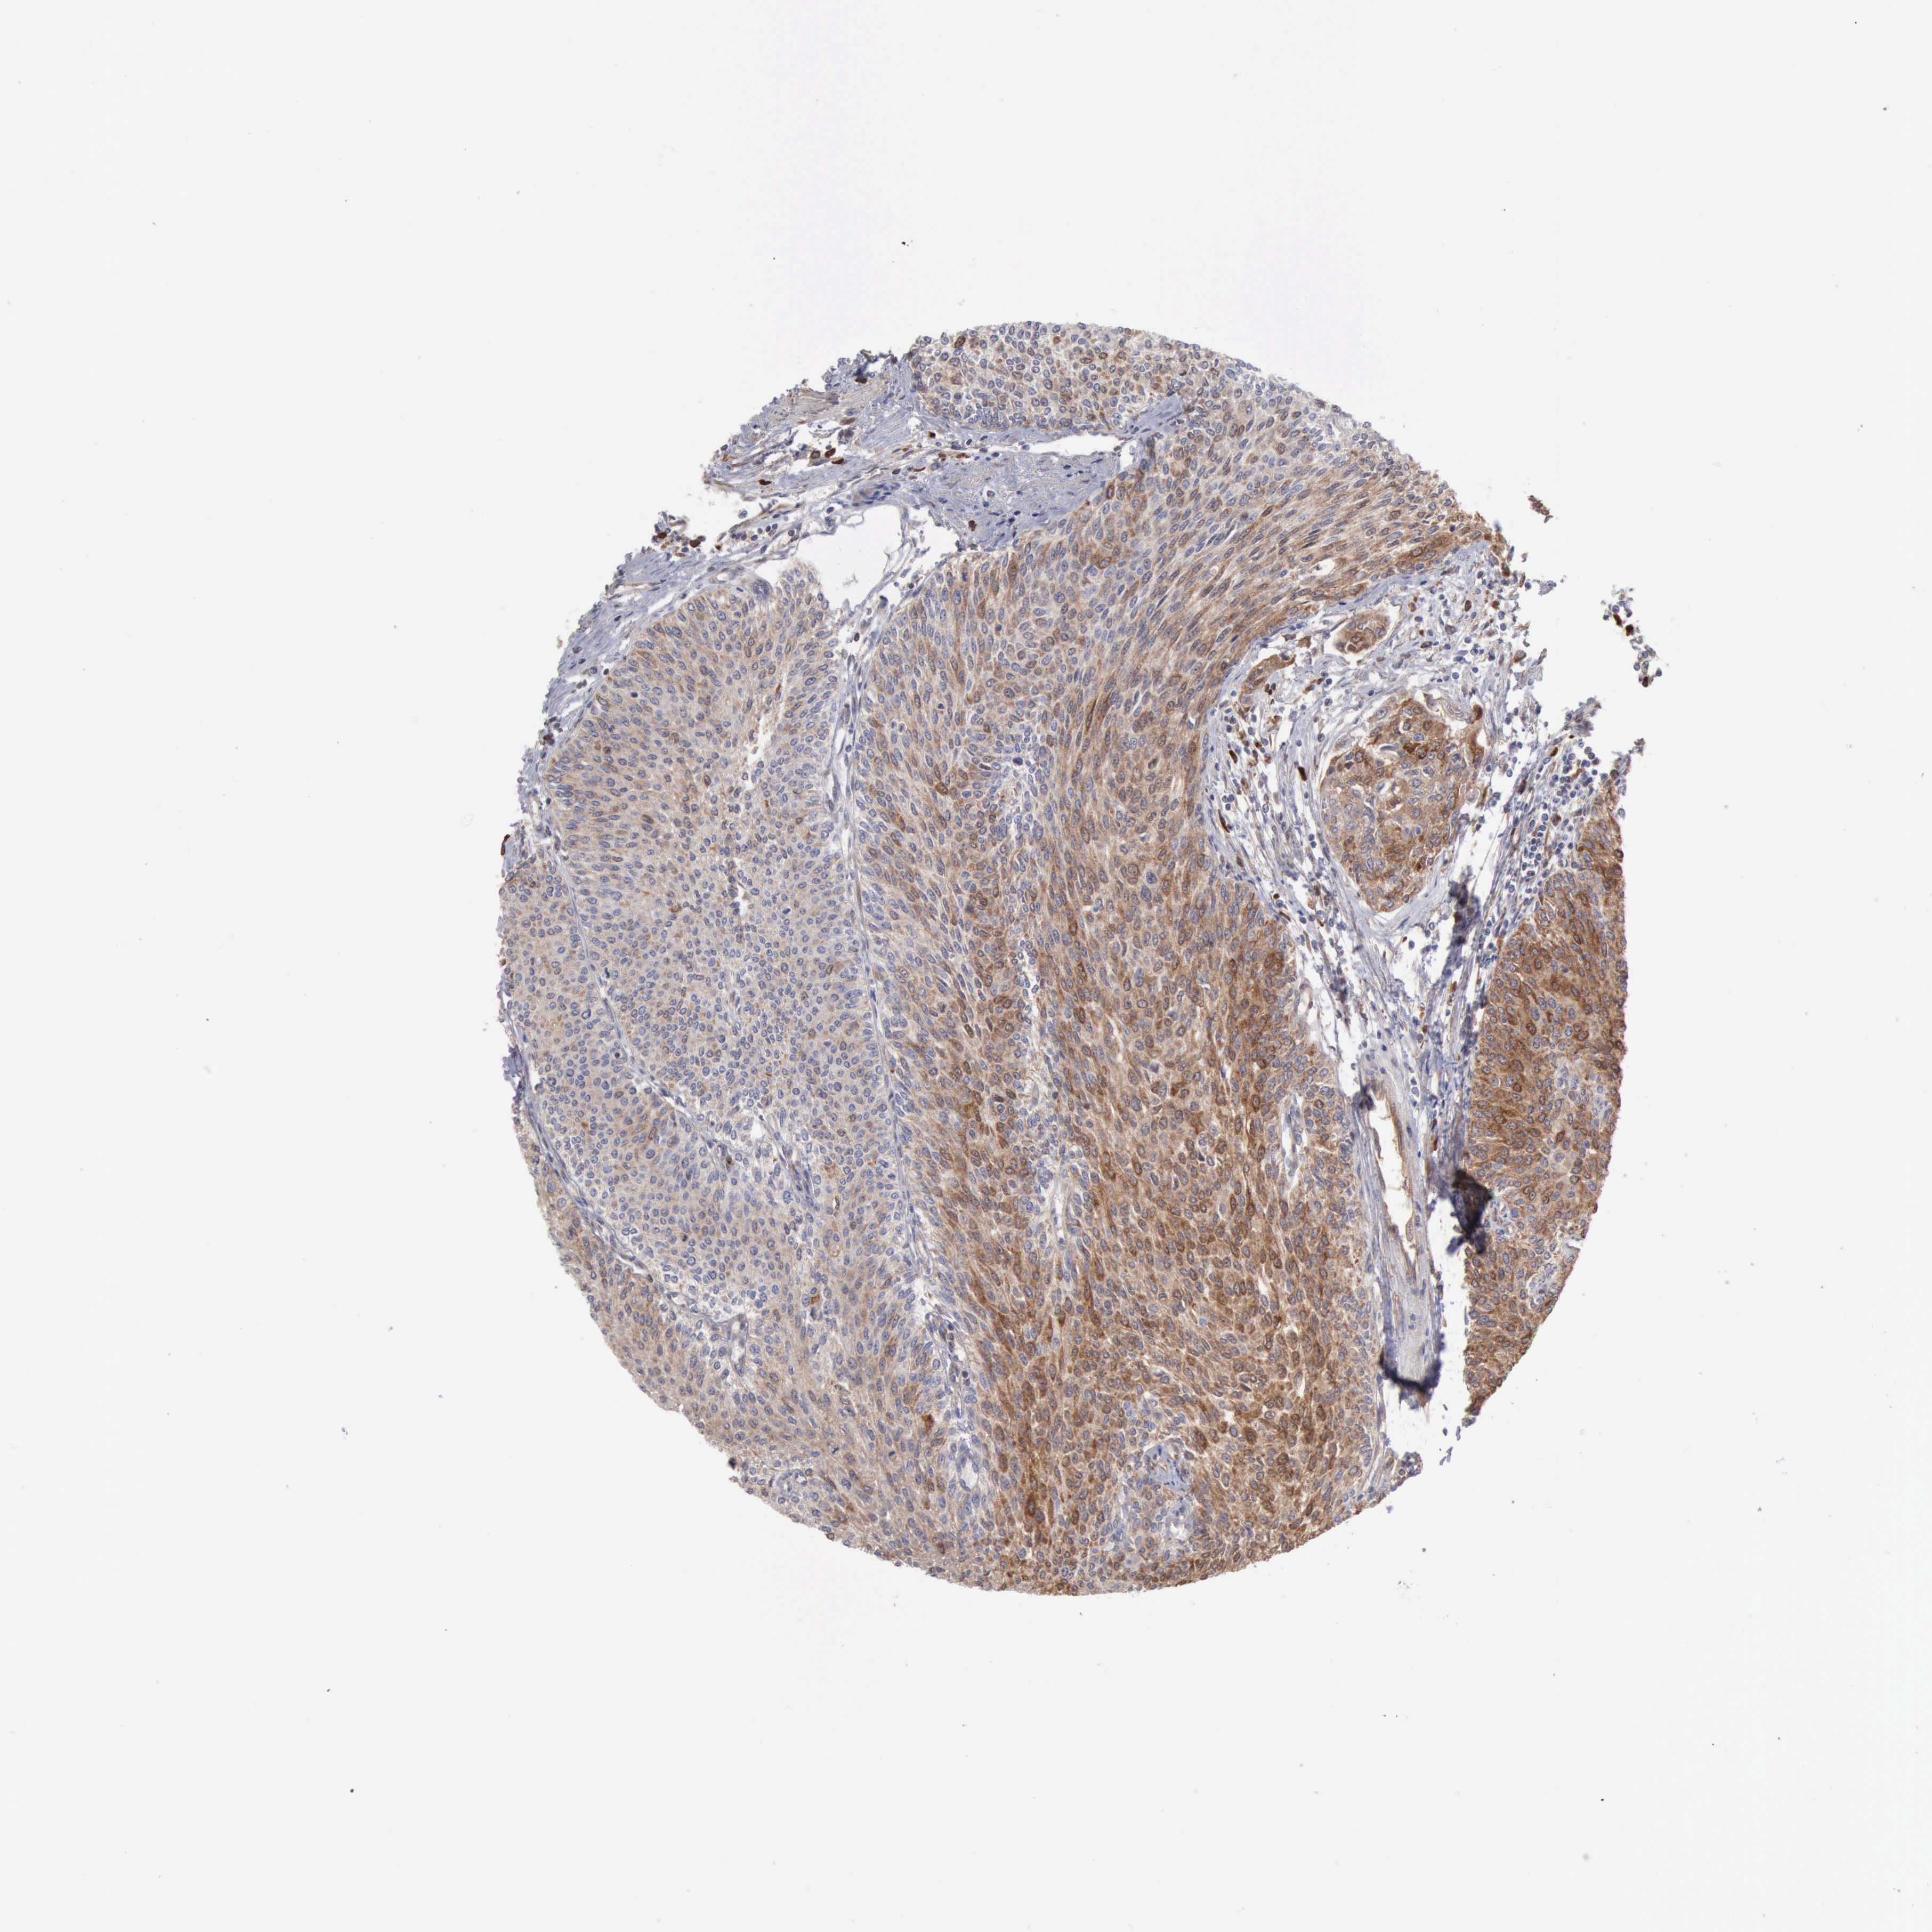

UROTHELIAL CANCER - Protein expressioni

A mouse-over function shows sample information and annotation data. Click on an image to view it in a full screen mode. Samples can be filtered based on level of antibody staining by selecting one or several of the following categories: high, medium, low and not detected. The assay and annotation is described here.

Note that samples used for immunohistochemistry by the Human Protein Atlas do not correspond to samples in the TCGA dataset.

Antibody stainingi

Antibody staining in the annotated cell types in the current human tissue is reported as not detected, low, medium, or high, based on conventional immunohistochemistry profiling in selected tissues. This score is based on the combination of the staining intensity and fraction of stained cells.

Each image is clickable and will lead to virtual microscopy that enables deeper exploration of all samples and also displays staining intensity scores, fraction scores and subcellular localization as well as patient and tissue information for each sample.

Antibody HPA001078

Antibody CAB026695

Staining

High

Medium

Low

Not detected

Intensity

Strong

Moderate

Weak

Negative

Quantity

>75%

75%-25%

<25%

None

Location

Nuclear

Cytoplasmic/membranous

Cytoplasmic/membranous,nuclear

Urothelial carcinoma, High grade

Urothelial carcinoma, Low grade